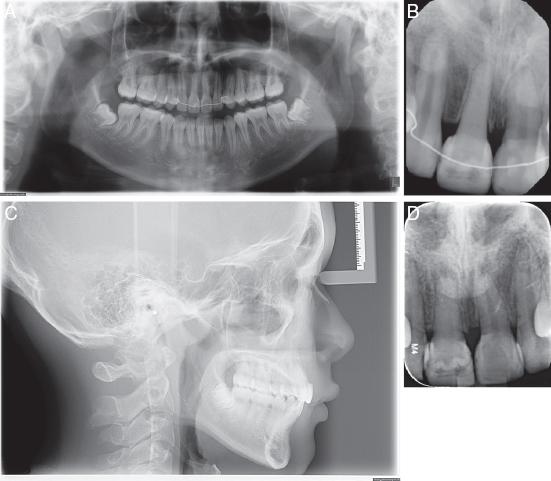

Figure 4.